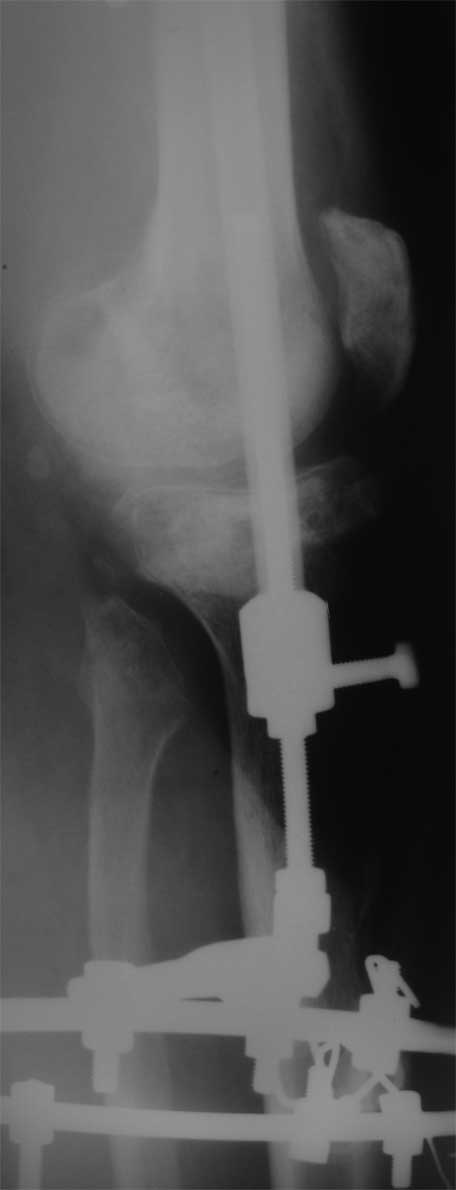

2. Хотелось бы увидеть снимки раннего периода, лучше после травмы, а также КТ. Интересует целостность плато б/б кости. По представленным

снимкам возникает подозрение, что наружный мыщелок отделен. Или это так кажется?

3. На данном этапе замещение костного дефекта - лишь часть проблемы.

У пациента жестокая эквинусная контрактура голеностопного сустава и почти наверняка - разгибательная в коленном суставе.

4. Представляется целесообразным снять аппарат и заняться ЛФК, направленной на разработку движений в коленном и голеностопном

суставах. При отсутствии перспектив восстановления движений в коленном суставе вполне можно задуматься об артродезе.

5. Если решать проблему замещения костного дефекта, то предложенный Павлом Ивановым вариант - наиболее реальный из известных, хотя и весьма сложный.

6. Готов предложить нестандартное решение в этой нестандартной ситуации. Межберцовое синостозирование в проксимальном отделе - между

головкой малоберцовой кости и наружным мыщелком. Это создаст дополнительную опору, которой может оказаться достаточно для функционирования.